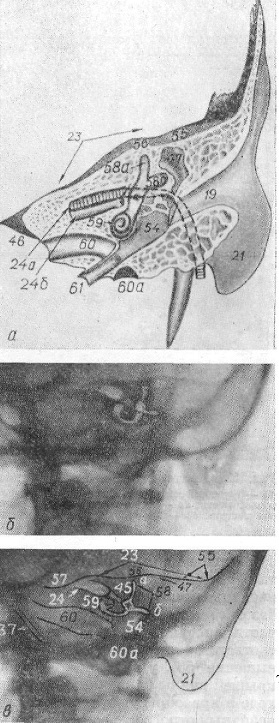

КТ анатомия сосцевидного отростка: особенности и показания

Раздел: Галерея прозрений